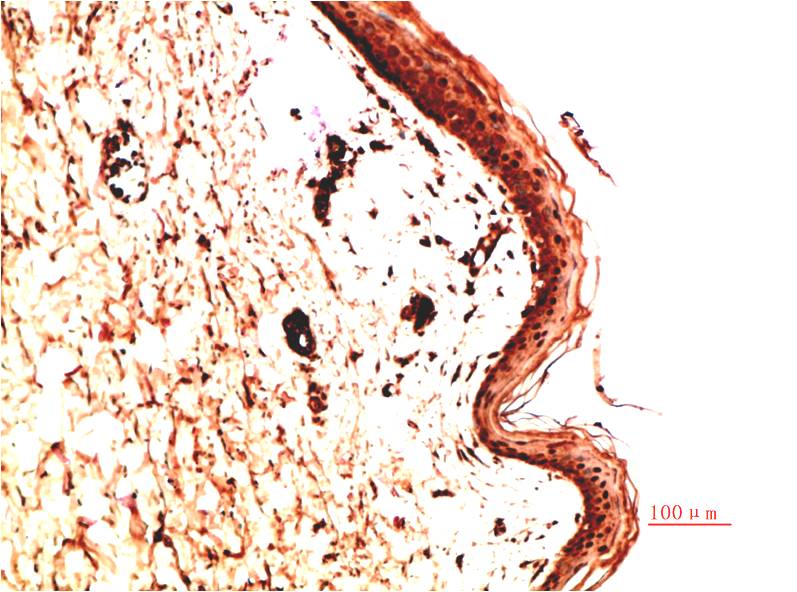

Collagen IV Mouse Monoclonal Antibody(5C9)

Catalog NO.:BE3725

Applications :IHC

Reactivity :H,R,M

Collagens are fibrous, extracellular matrix proteins with high tensile strength and are the major components of connective tissue, such as tendons and cartilage. All collagens contain a triple helix domain and frequently show lateral self-association in order to form complex connective tissues. Several collagens also play a role in cell adhesion, important for maintaining normal tissue architecture and function.

Recommended dilutions: IHC: 1:100-200

Specificity: The antibody can detects endogenous Collagen IV proteins.